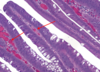

What condition does this person have?

What is being stained in the image on the right?

Peutz-Jegher syndrome

Muscle actin stain - reveals arborizing smooth muscle